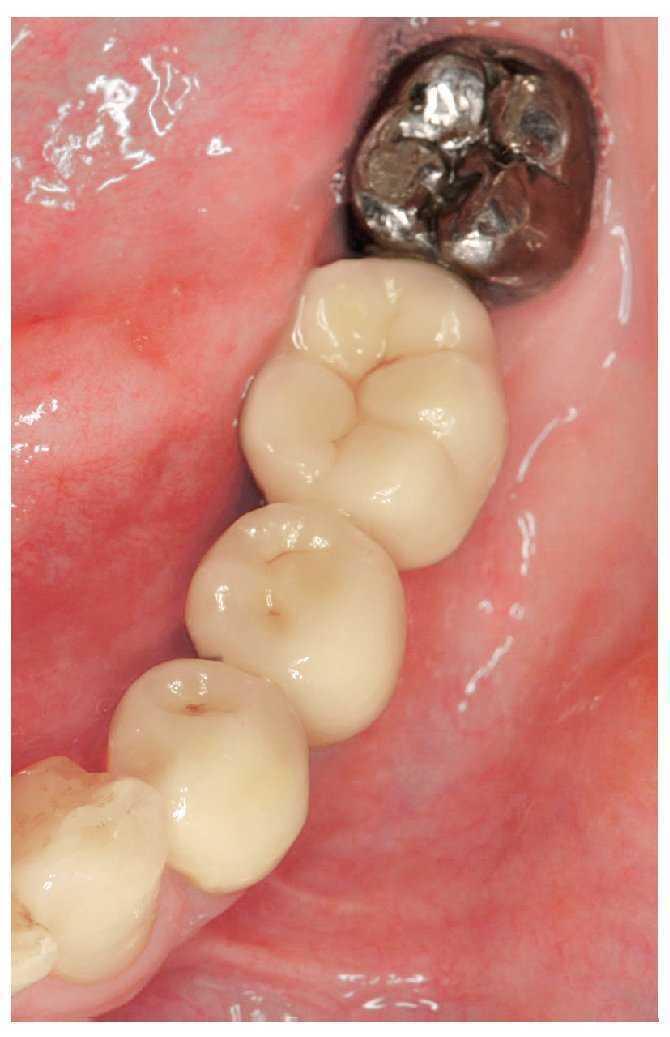

Figura 4a. Ausencia del diente 36, diente 35 sin caries y obturación oclusal en el diente 37.

Figura 4b. Puente adhesivo de metal cerámica de doble aleta que incluye la obturación oclusal.